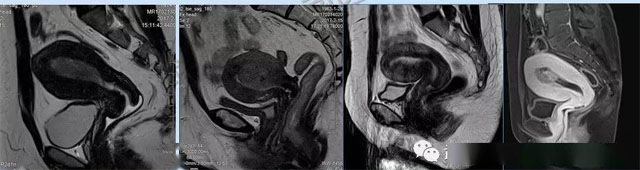

婦科疾病常常讓女性陷入了焦慮。主要是這類疾病婦女有難言之隱,癥狀隱匿,病情復(fù)雜。磁共振體檢車的金光火眼能力可以破解各種婦科難題。哪些情況需要使用磁共振檢查,檢查過(guò)程是否有不適。這些都是可以解決的。例如子宮常見(jiàn)疾病的磁共振診斷。

磁共振VS傳統(tǒng)檢查:有這些優(yōu)勢(shì)?無(wú)輻射安全系數(shù)高,磁共振沒(méi)有電離輻射,適合備孕跟孕婦檢查。它對(duì)軟組織有高清的成像效果,可以清晰的看到子宮各層的結(jié)構(gòu)。可以識(shí)別細(xì)小的肌瘤,早期的癌癥腫瘤??梢园l(fā)現(xiàn)其他設(shè)備難以檢查到的深部子宮內(nèi)膜異位結(jié)節(jié)。多序列成像和增強(qiáng)掃描檢查,判斷腫瘤的良性準(zhǔn)確率高達(dá)90%以上。